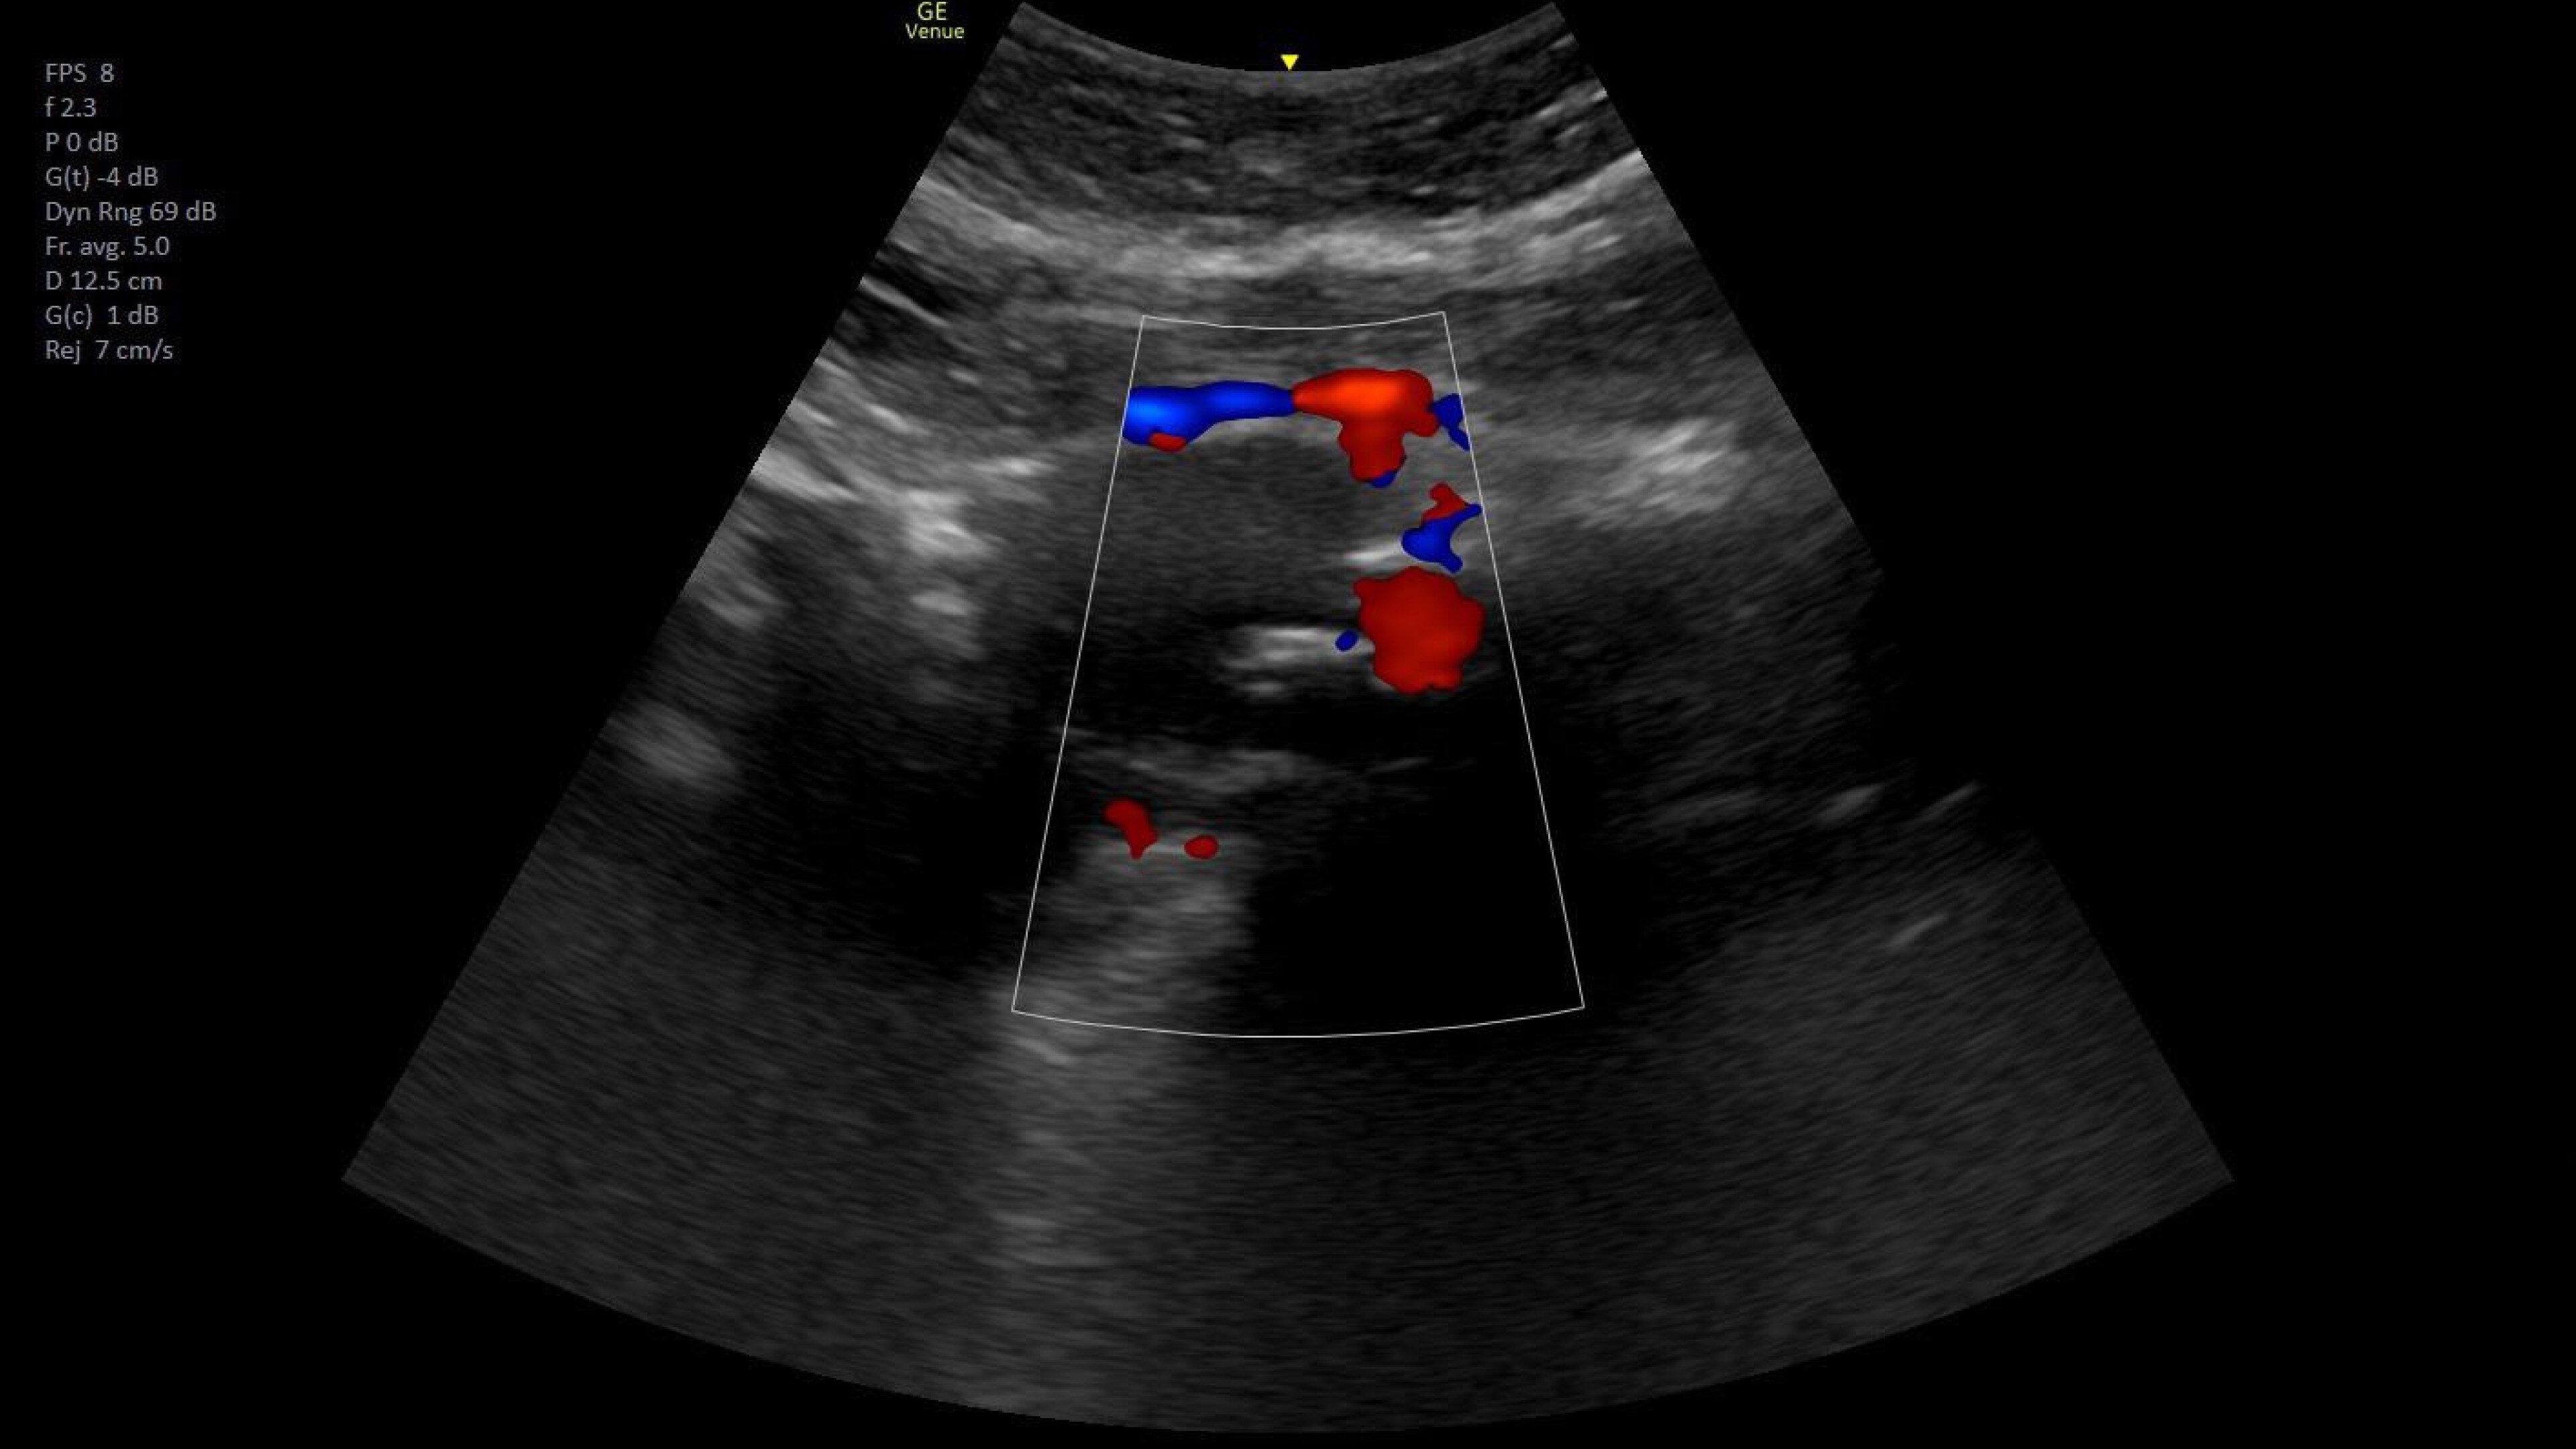

Vascular access

Helps you to assess vascular diseases, from cardiovascular conditions and peripheral vascular disease to pulmonary vascular disease.